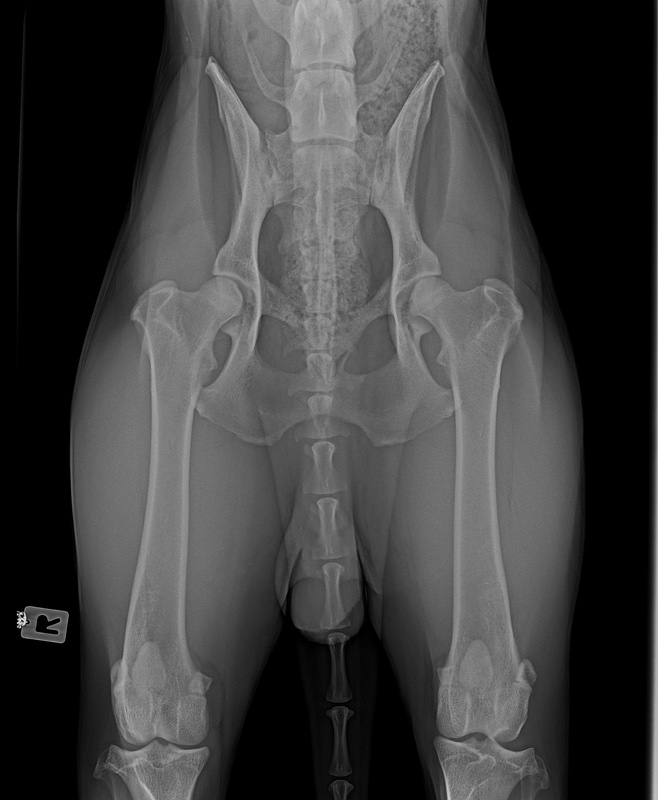

Hattest Du ein "B" erwartet ? Bist Du enttäuscht ?

Ich hätte mich natürlich sehr über A gefreut. Aber B ist ja auch noch ok.

Wir warten jetzt mal die offizielle Auswertung ab. Bin auch gespannt, was nun bei OCD und Lendenübergangswirbel rauskommt. Und welcher LÜW-Typ.

"Totalausfall" ist er mal definitiv keiner, und der Übergabg von A zu B ist sooo minimal... ich kann mir gut vorstellen, dass du vom Gutachter trotzdem A bekommst... würde jetzt mal abwarten.